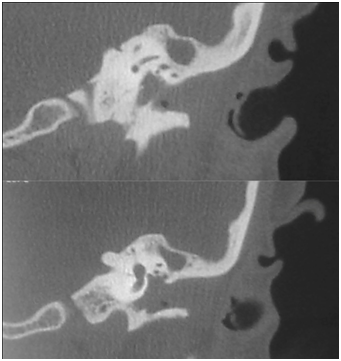

CT scan temporal bone shows left mastoid cells occupied by soft tissue density suggestive of chronic disease and EAC with the presence of soft tissue density, the tympanic cavity is also occupied by same soft tissue density that erodes its walls and no ossicular chain is observed. Carotid artery, jugular fossa, semicircular canals, cochlea and other structures unchanged (Figure 2). The right ear is normal. The skull MRI shows a hypointense occupying the left EAC on T1 that becomes hyper intense in T2 sequence and shows a heterogeneous enhancement when contrast is applied (Figure 3).

Figure 2A Coronal CT scan with tumor in the EAC and tympanic cavity; lysis of the tympanic membrane and oscicular chain.

Figure 2B Coronal CT Scan with erosion of the posterior wall of the EAC.